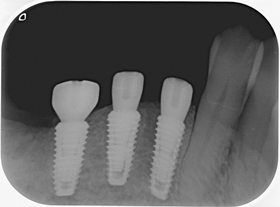

分別植牙後X光片